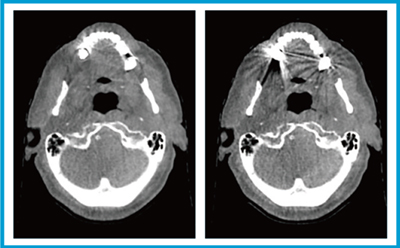

HyperSightを用いたARTの実践

今回,当院ではHyperSightを用いて,頭頸部癌に対しoffline-ARTのワークフローでARTを実践した。実際に初回CTのCTVやGTV,PTVをCBCTの画像に重ねると,顎下腺やリンパ節のずれ,痩せが認められた(図1)。また,CBCTの画質が驚くほど向上し,より客観的な判断が可能になったと感じた。ビームおよびMUを変えずに,CBCT上で線量計算してみると,喉頭線量がmean dose 67 Gyを超えており,PTVの最大線量が処方線量の113%と非常に高くなっていた。これでは実施不可で,リプランを実施するという判断をすることになった。このような判断をカウチ上で行えることになる。

図1 HyperSightによるoffline-ARTワークフローの改善